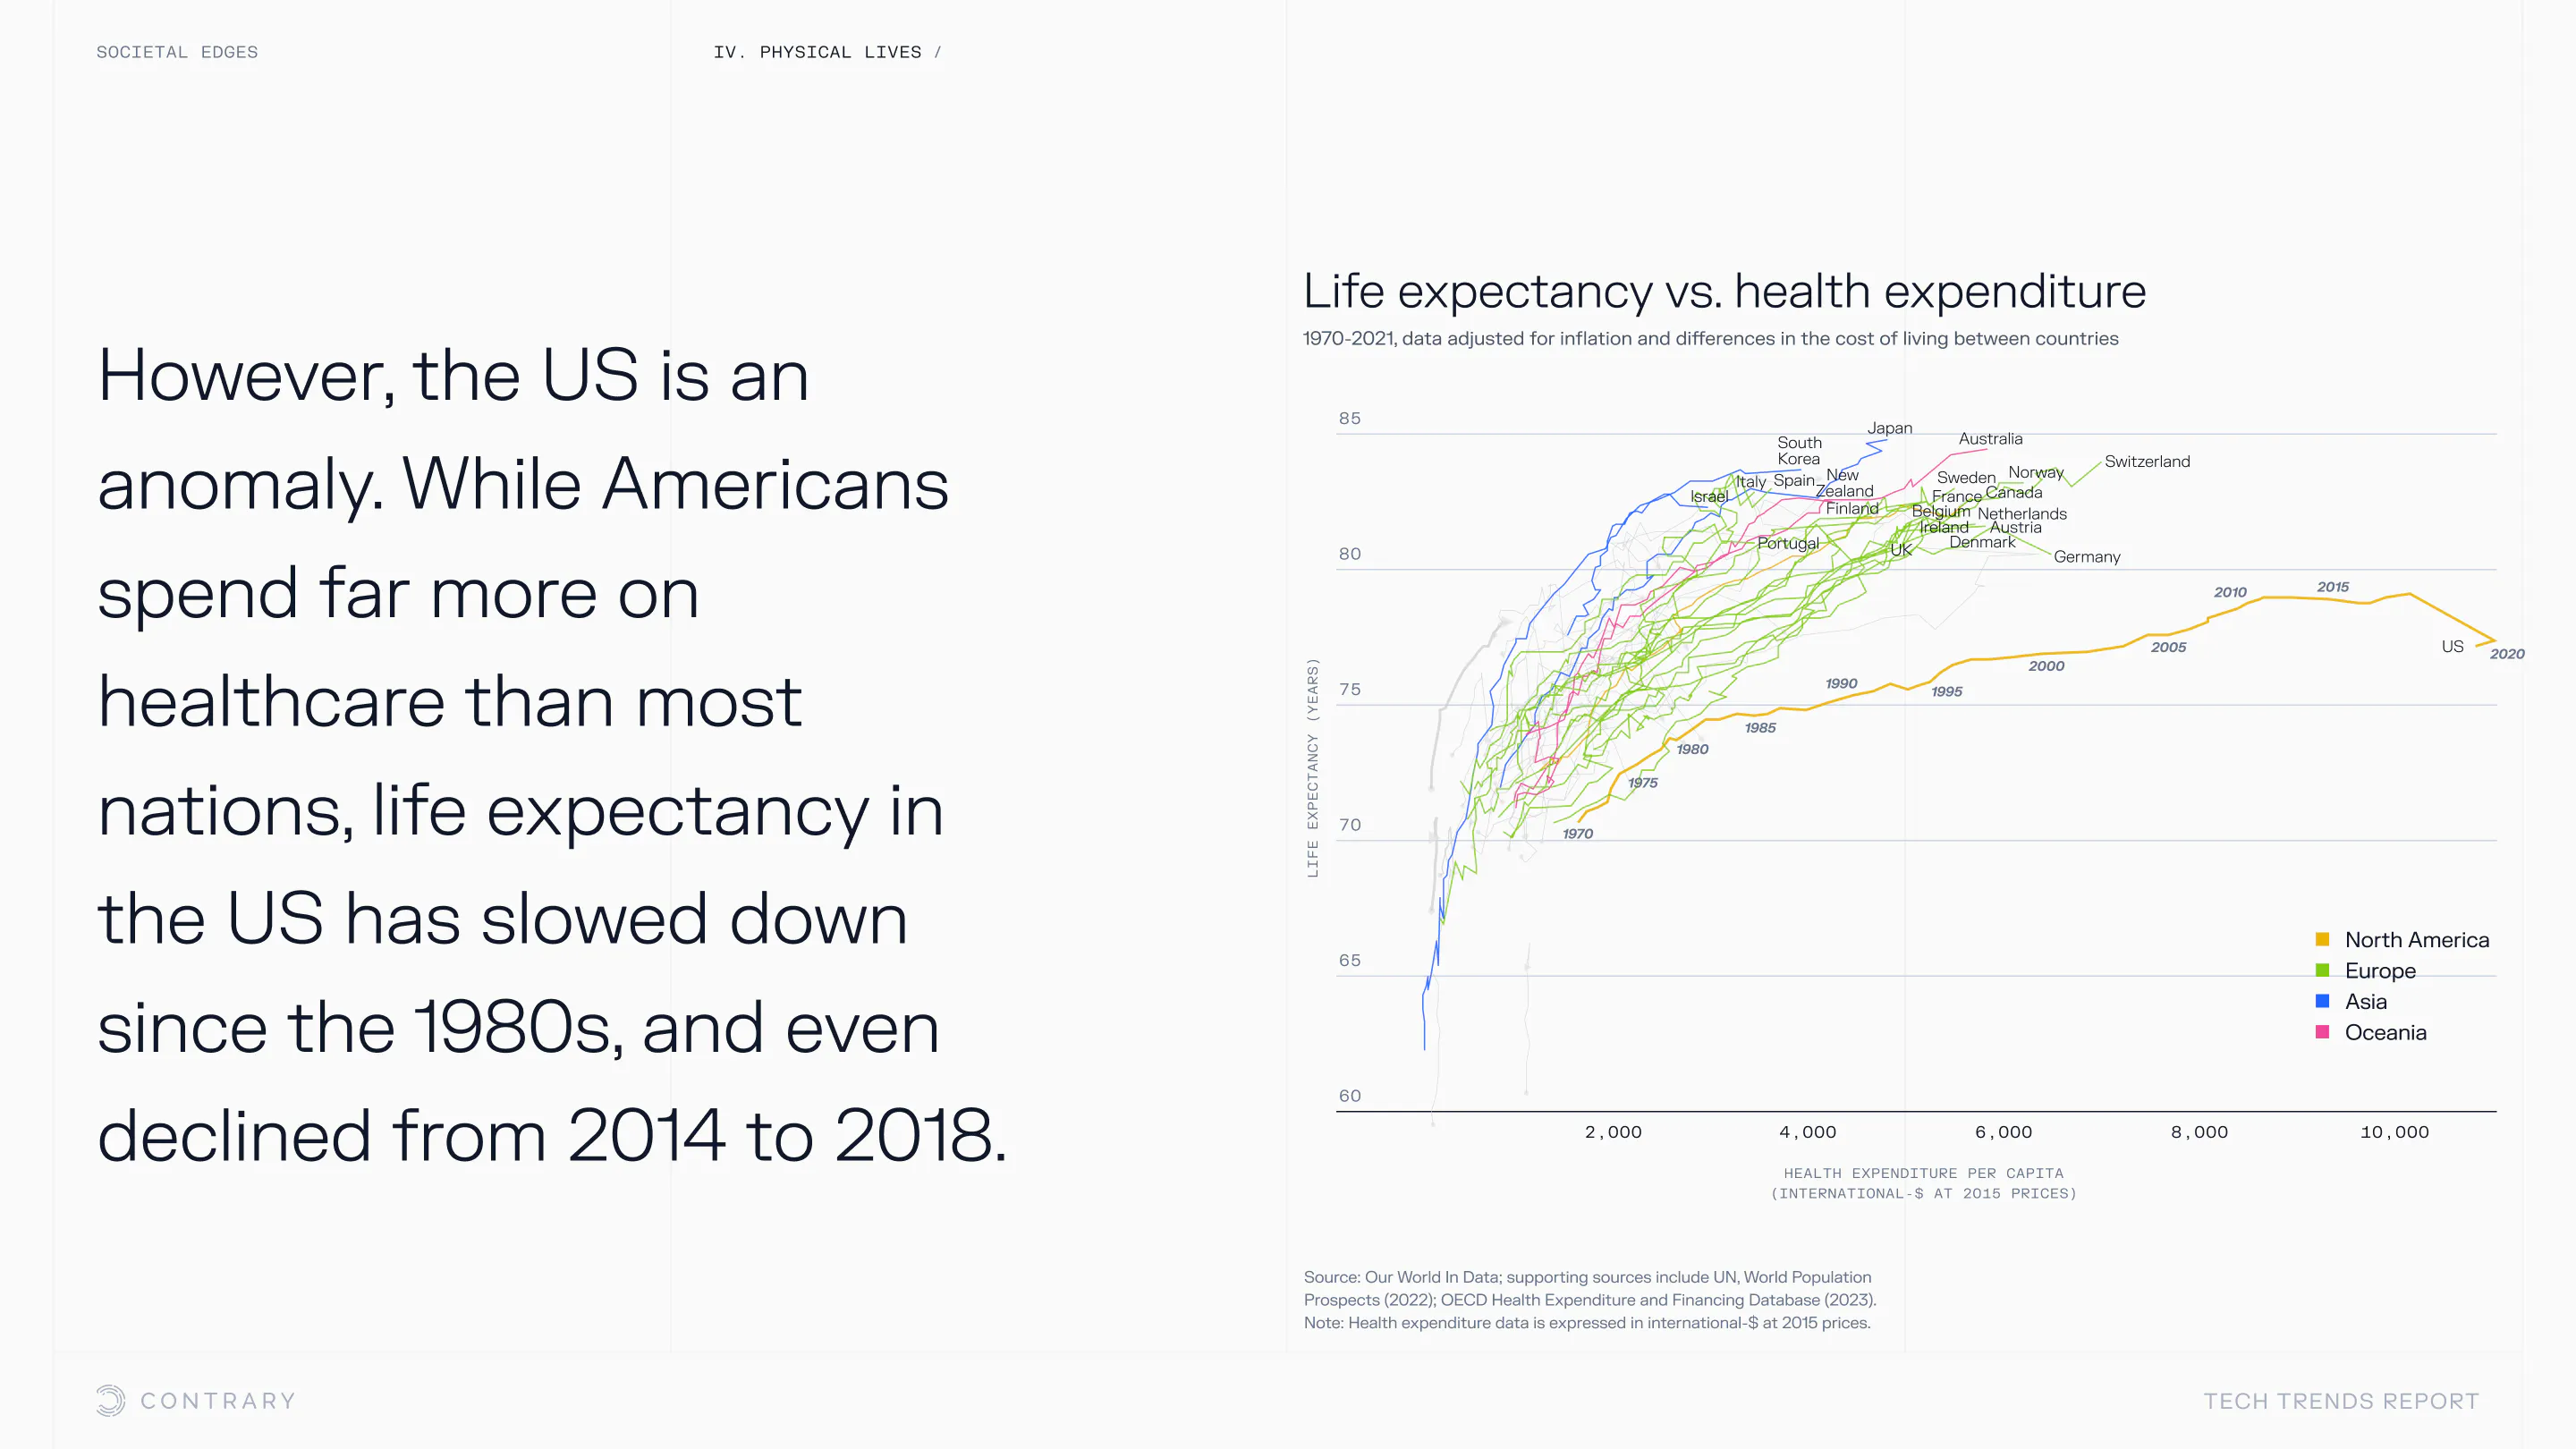

An aging population is bringing up a range of increased concerns, from mental health to disease control. Obesity and gastrointestinal cancers are plaguing younger generations. The cutting edge is tackling a system that has unhealthiness woven into it.